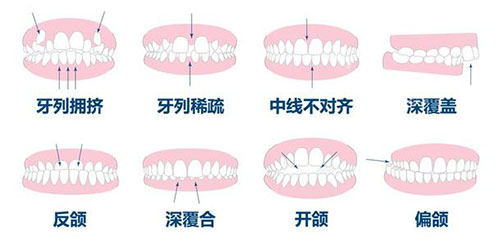

牙齿矫正项目价格表

| 传统金属托槽矫正 | 6000-20000起 |

| 金属自锁托槽矫正 | 10000-15000起 |

| 陶瓷托槽矫正 | 10000-25000起 |

| 隐形矫正(国产) | 20000-40000起 |

| 隐形矫正(进口) | 30000-55000起 |

| 隐适美Comprehensive系列 | 40800起 |

| 儿童早期矫正 | 4000-10000起 |

患者B:牙齿矫正体验